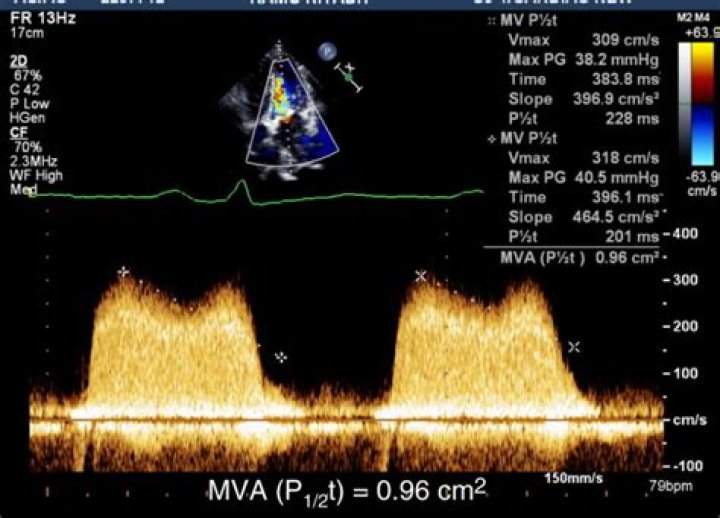

How does PHT measure MVA?

The PHT of the mitral inflow deceleration slope was determined from the stored mitral inflow Doppler VTI, and the MVA was then calculated using the following formula: MVA = 220/PHT (Figure 1) [10].

How do you calculate PHT?

The time from the Vmax to the velocity equal to Vmax divided by 1.4 is the pressure half time. (Vmax / 1.4 is equivalent to the half pressure). 220 divided by the PHT is the mitral valve area.

How do you calculate pressure in halftime echo?

Calculation of the pressure half-time (PHT) is achieved by measuring the time from peak E wave velocity (V1) to the point when velocity equals peak velocity × 0.71 (V2) (calculations in white) and by measuring the deceleration time from the extrapolated E–F slope and multiplying by 0.29 (calculations in yellow) (D).

What is pressure half time used for?

Doppler echocardiography is useful in assessing the severity of obstructive cardiac lesions, such as mitral valve stenosis. The Doppler study can be used to calculate pressure half-time (PHT), which is defined as the time required for the pressure gradient across an obstruction to decrease to half of its maximal value.